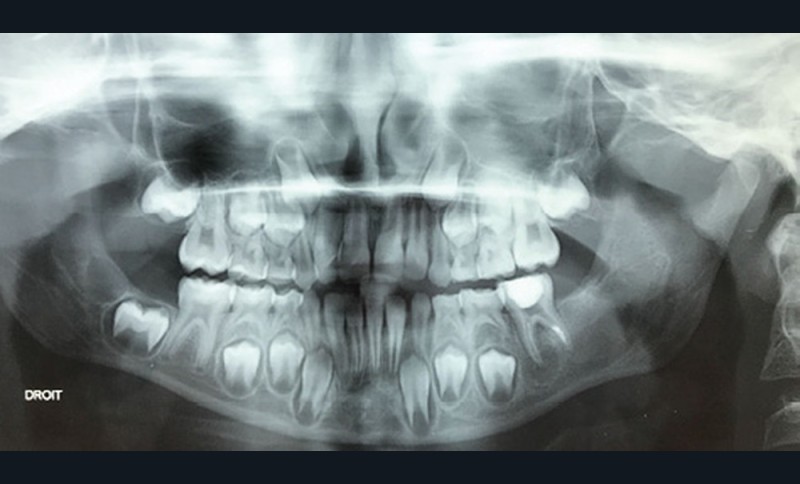

Les kystes et tumeurs bénignes osseuses maxillaires ou mandibulaires chez l’enfant sont le plus souvent asymptomatiques. Ces lésions osseuses sont découvertes de façon fortuite lors d’un bilan radiographique de routine réalisé par l’odontologiste pédiatrique ou l’orthodontiste [1-3]. Néanmoins, des lésions peuvent parfois se développer rapidement et être destructrices [1, 2]. Certains signes cliniques spécifiques à la chronologie de l’éruption dentaire chez l’enfant doivent nous alerter tels qu’un retard d’éruption dentaire ou une éruption dentaire asymétrique (fig. 1). D’autres manifestations cliniques, moins spécifiques à l’enfant, peuvent également orienter le clinicien sur la présence d’une pathologie osseuse sous-jacente : mobilité dentaire, douleur, tuméfaction, limitation de l’ouverture buccale, trouble neurosensoriel, etc. [3]. C’est la radiographie panoramique qui va ensuite mettre en évidence/confirmer la présence d’une lésion intra-osseuse (fig. 2).

La radiographie panoramique permet une première interprétation de la lésion osseuse (localisation, nombre, taille approximative, etc.). Cet examen est souvent complété par un bilan d’imagerie en trois dimensions de type Cone Beam [4]. Il précisera le volume et les limites de la lésion ainsi que ses rapports avec les structures anatomiques avoisinantes (tableau 1). Ces données radiologiques confrontées à l’examen clinique et à la fréquence relative des lésions permettent de réaliser un diagnostic d’intuition qui orientera la prise en charge.